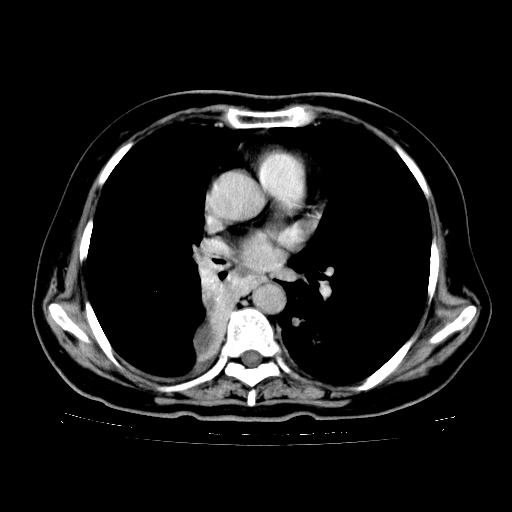

标题: CT23067:女,70岁,咳嗽、咳痰一个月,低热一周。 [打印本页]

女,70岁,咳嗽、咳痰一个月,低热一周。

1.左上肺结核,部分纤维化。右肺中下叶部分肺不张,内见液化、坏死及点状钙化,右中下叶支气管壁增厚、管腔狭窄,见多个点状钙化,结合临床考虑支气管内膜结核,建议痰检查抗酸杆菌并参考血沉。两肺多个小圆点状高密度灶,境界模糊,多考虑结核肺内播散。但本人年龄较大首先应支气管镜检以除外右肺癌。

2.胸主动脉夹层。

支持,首先一元论解释。胸主动脉部分层面环形低密度,中心强化。环形影不强化。不象真假腔的改变。我考虑动脉炎,不太支持夹层动脉瘤-和大家的观点不一致,希望楼主让患者再做个心血管的彩超吧。